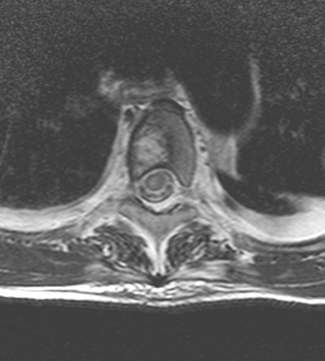

Syrinx describes the condition when cerebrospinal fluid enters the interior of the spinal cord and forms a cavity in its center in a tube or a flute- like manner. It can even be a few segments long.

MRI: only MRI can provide a definitive diagnosis by depicting the expanded region within the axis of the spinal chord as an expansile lesion showing liquor intensity on all sequences (weak T1 signal and strong on T2 weighted imaging).

MRI: On T1W images they are isointense with the spinal chord. On T2 weighted images they have a high signal intensity and appear as a mass expanding the spinal chord.

MRI: On T1 withed images it shows isointense with the spinal chord, while on T2W images it is hyperintense.